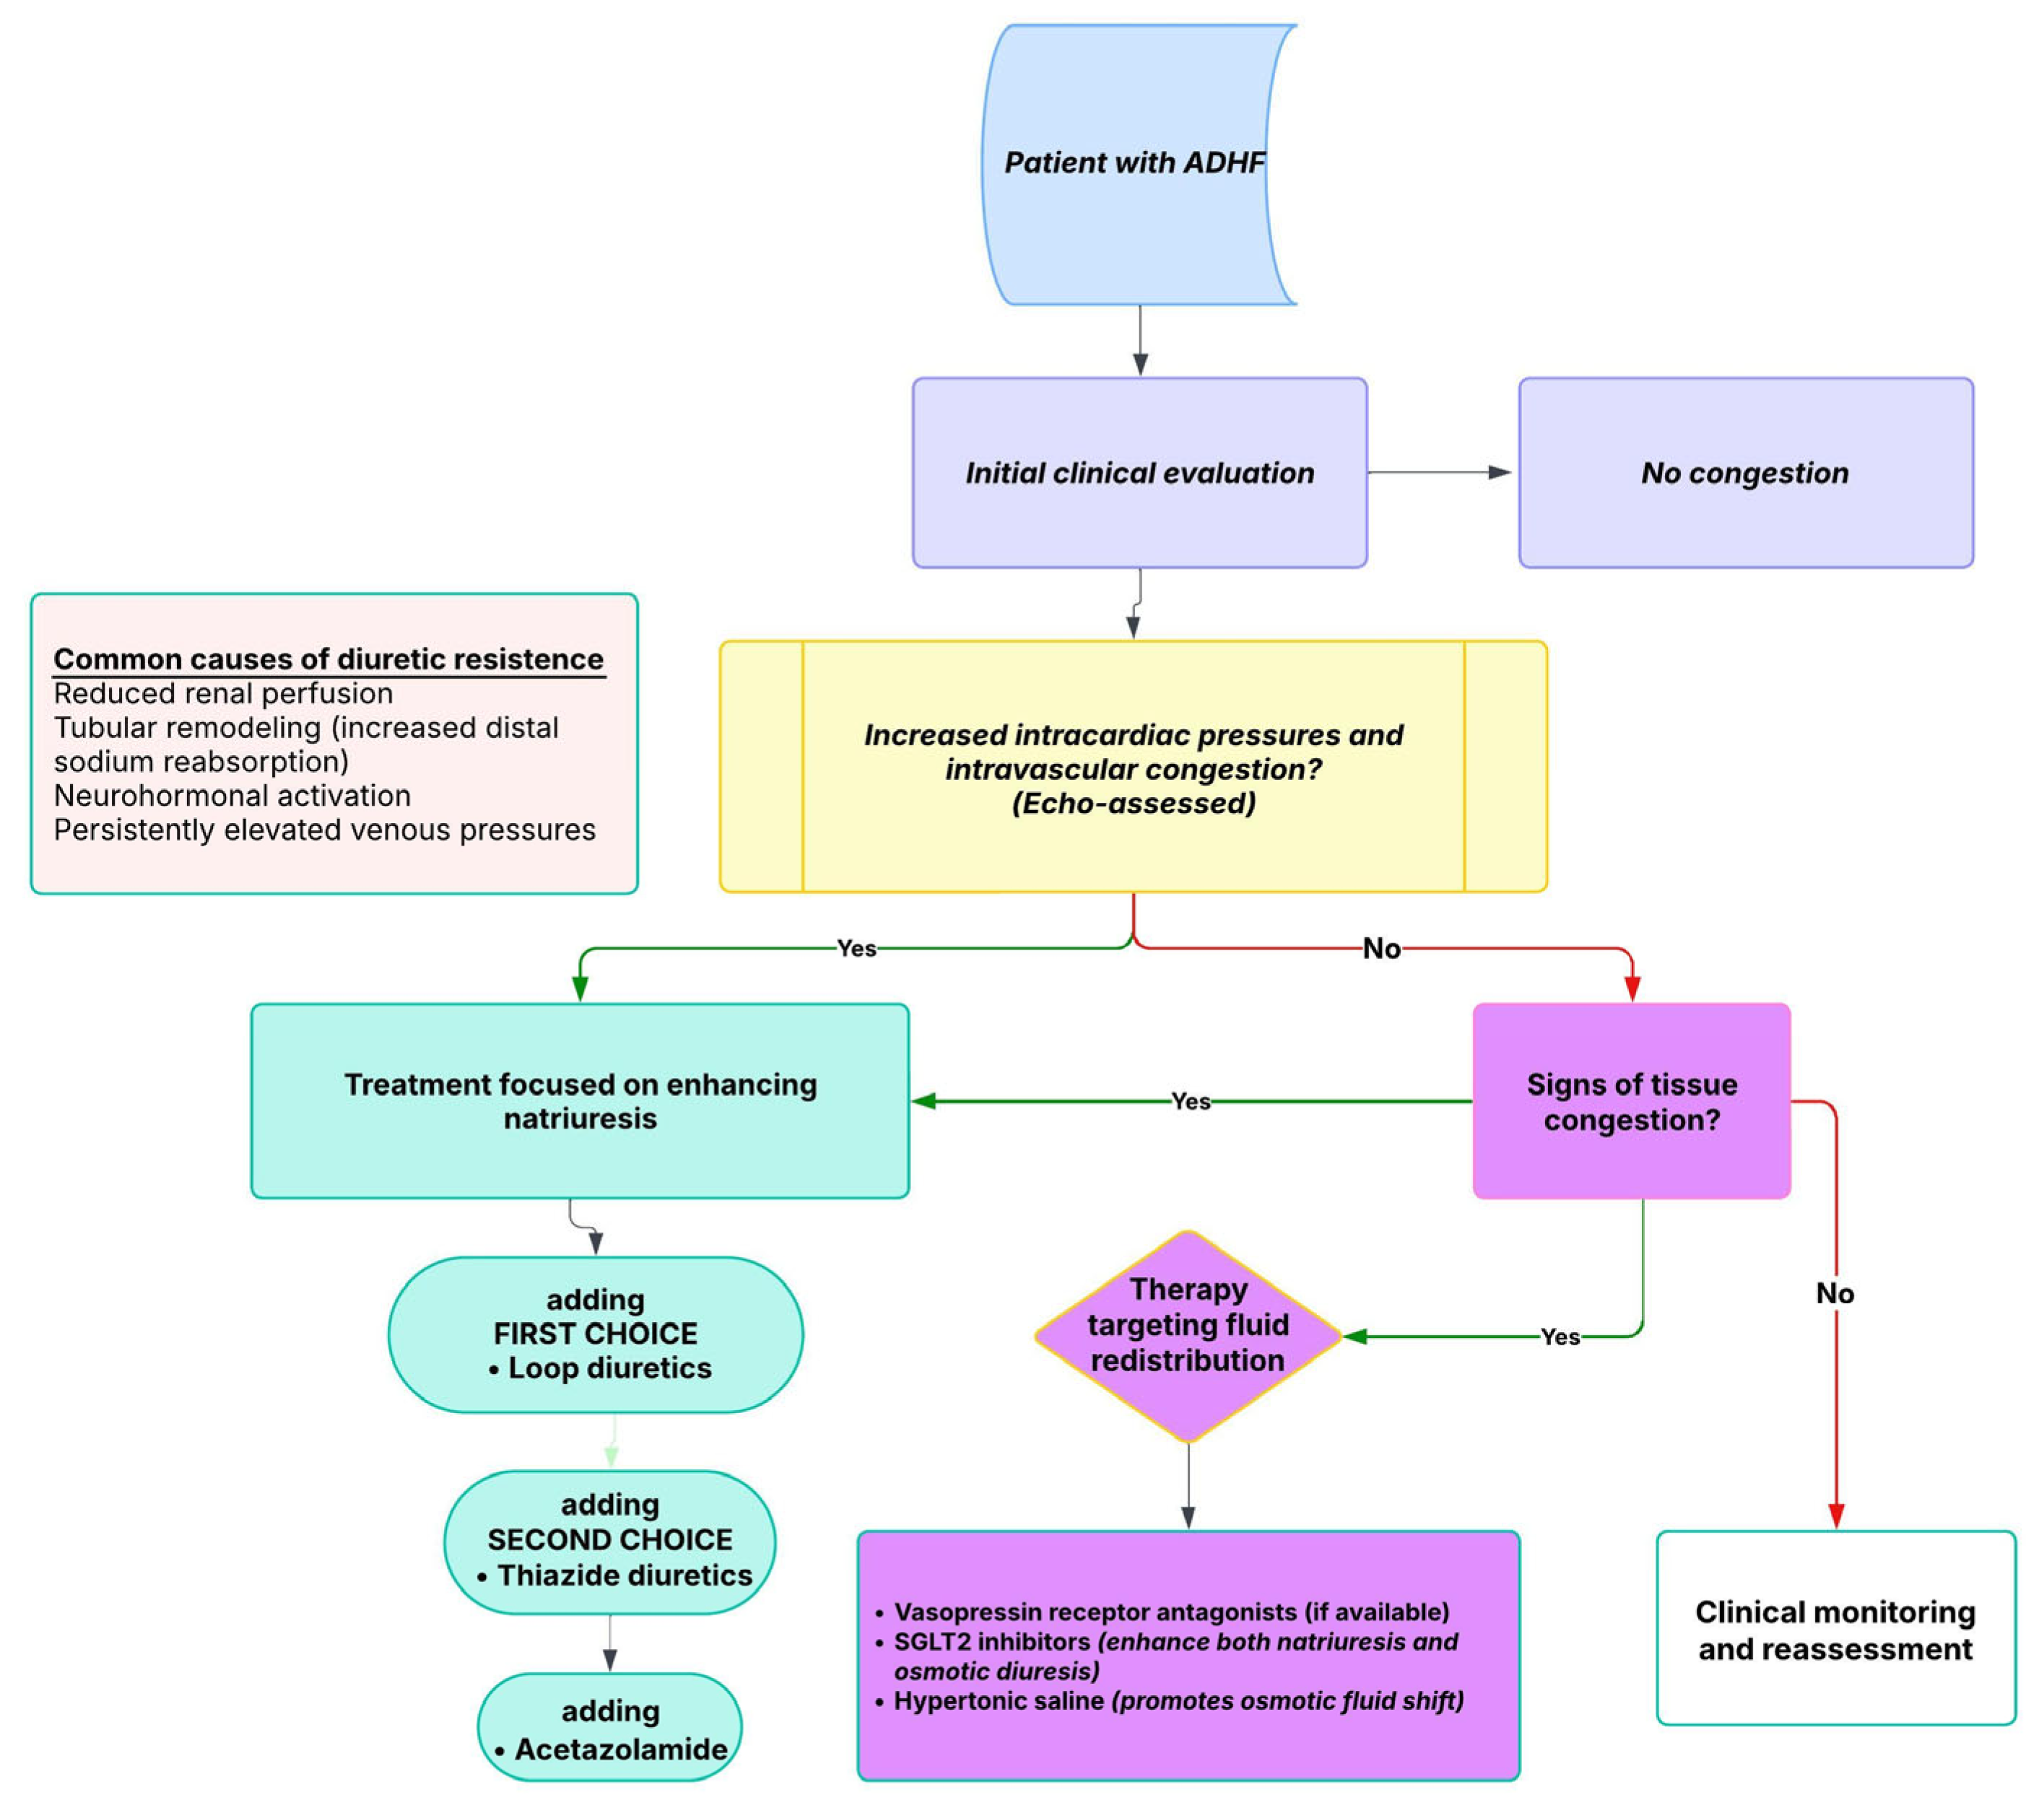

7. Integrated Multimodal Assessment and Clinical Application

8. Intravascular vs. Tissue Congestion: Implications for Diuretic Strategy and Resistance

Diuretic Resistance in HF